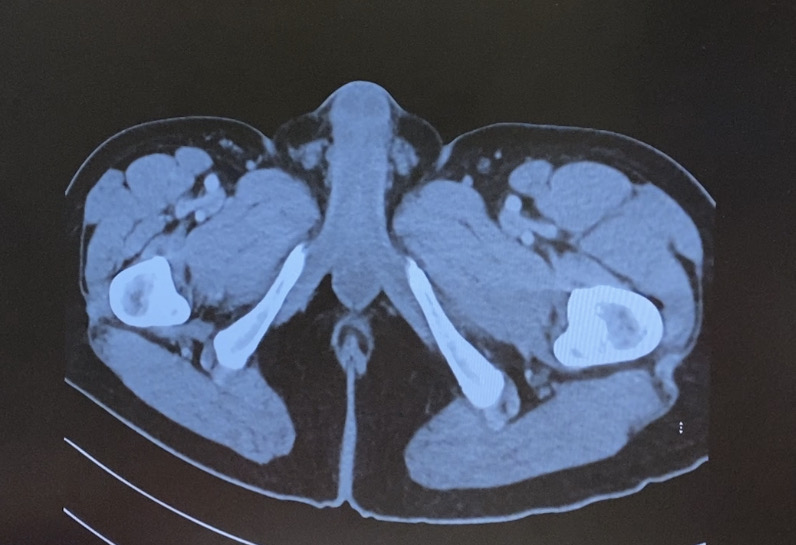

Day 109 – My Full Body Lymphoma CT Scan in nude